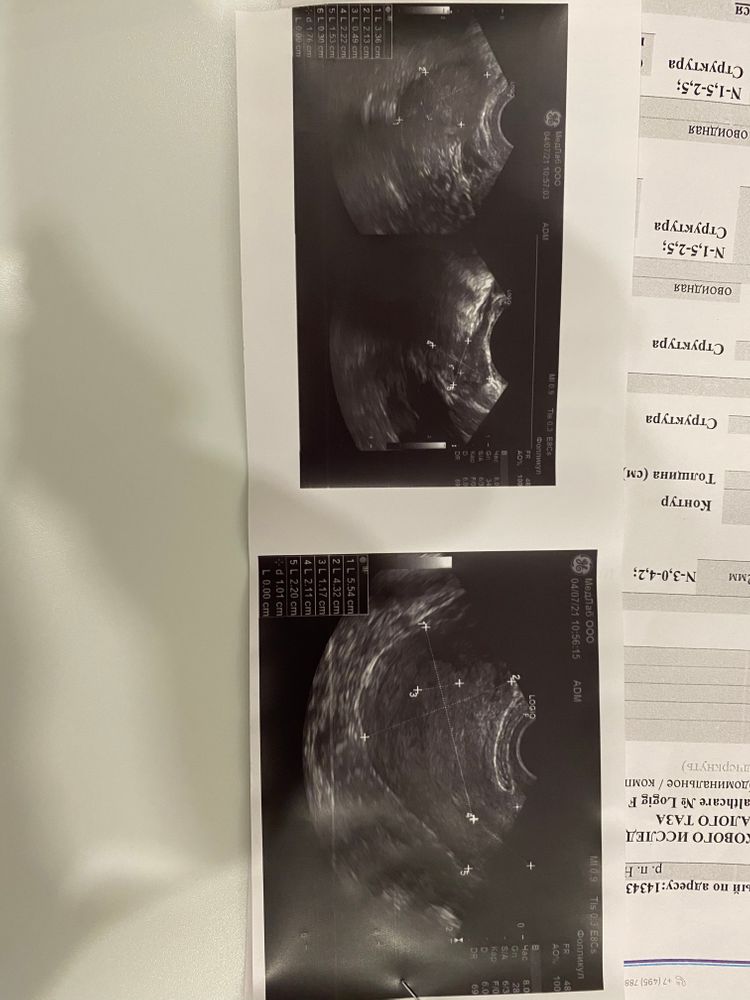

Добрый вечер, извините, что так поздно отвечаю вам . Вот делали трансвагинальное узи, сказали все хорошо по узи